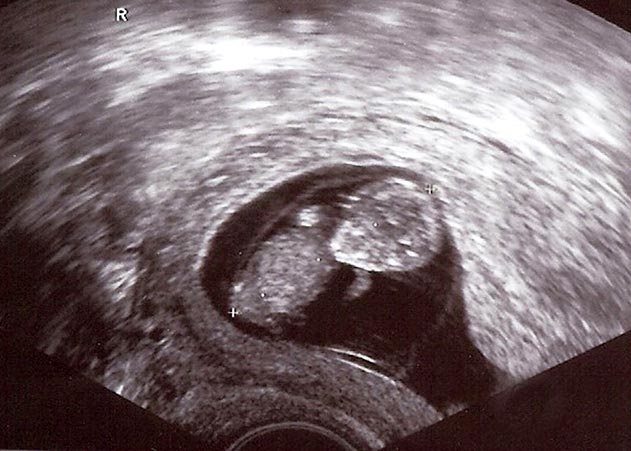

Jena. Erste Vierlingsgeburt seit zwölf Jahren in Thüringen: Albanische Frau entbindet im Uniklinikum Jena.